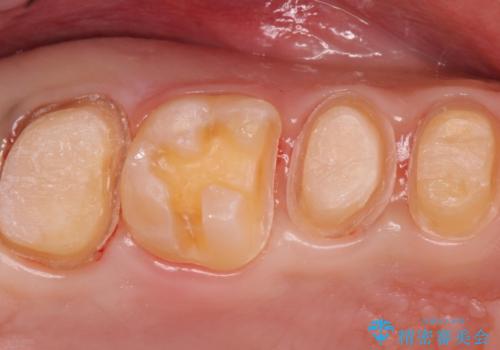

奥歯は十分な歯の高さがなかったため、クラウンをかぶせる前に歯周外科治療で歯の高さを出しています。

歯科に通うようになってから磨き残しの状態も改善されていきました。